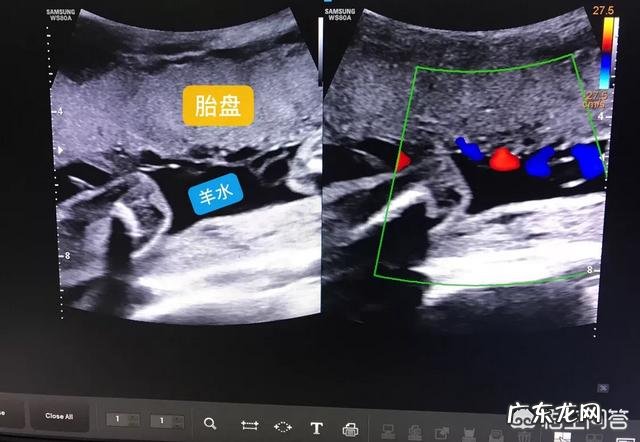

羊水条件:超声医生在观察胎儿的时候常会以羊水为透声窗,目的就是为了观察得更清楚 。如果羊水过少等羊水原因,也会增加检查难度 。